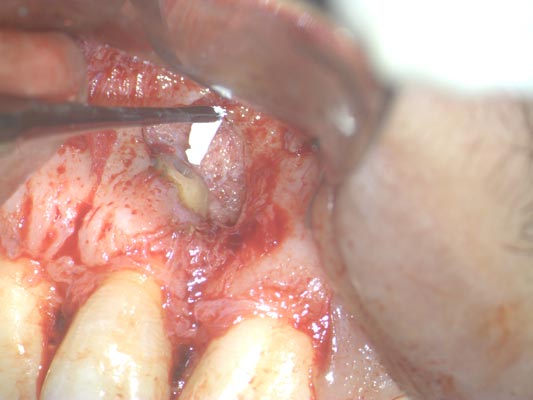

Imágenes:

Radiografía previa y final del tratamiento.

Medimos el ápice, retiramos el relleno anterior y colocamos relleno biocompatible.